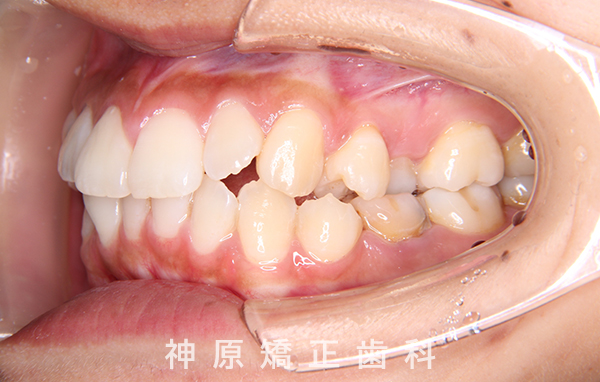

初診時

マルチブラケット装着1年後

治療終了